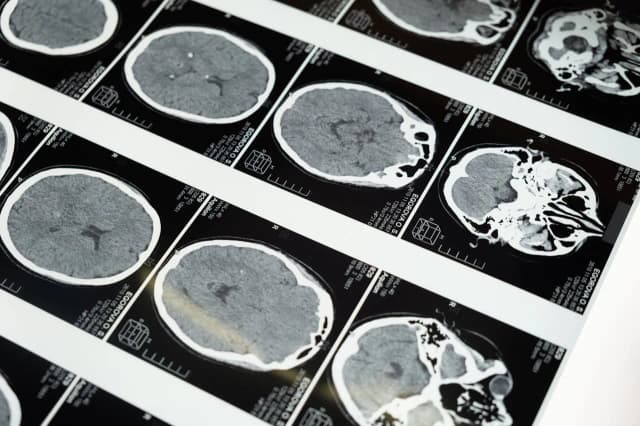

Jakie są przyczyny udaru mózgu? Zrozum ryzyko i jak je zmniejszyć

Dowiedz się, jakie są przyczyny udaru mózgu oraz poznaj modyfikowalne czynniki ryzyka i objawy. Zwiększ swoją wiedzę na temat profilaktyki udaru mózgu!